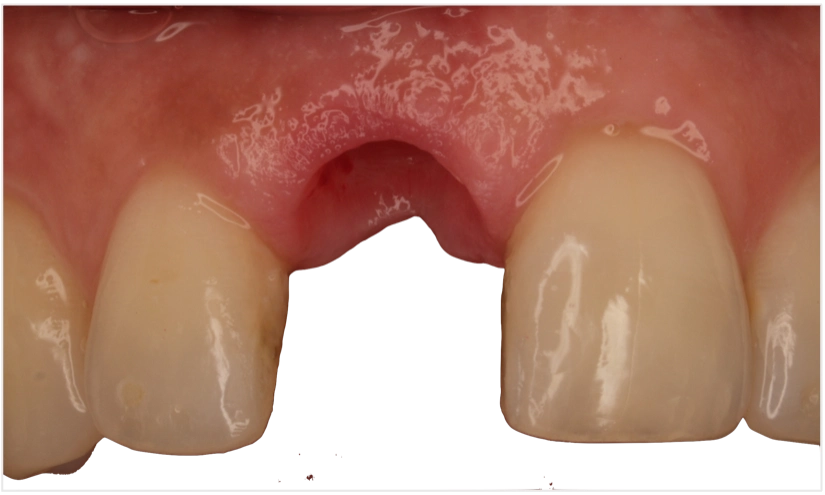

Case Study 1: Complex Anterior Replacement

- Challenge: High smile line with thin biotype

- Solution: Digital planning with photogrammetry-guided surgery

- Outcome: Perfect emergence profile and colour match

- Time: 60% faster than traditional workflow